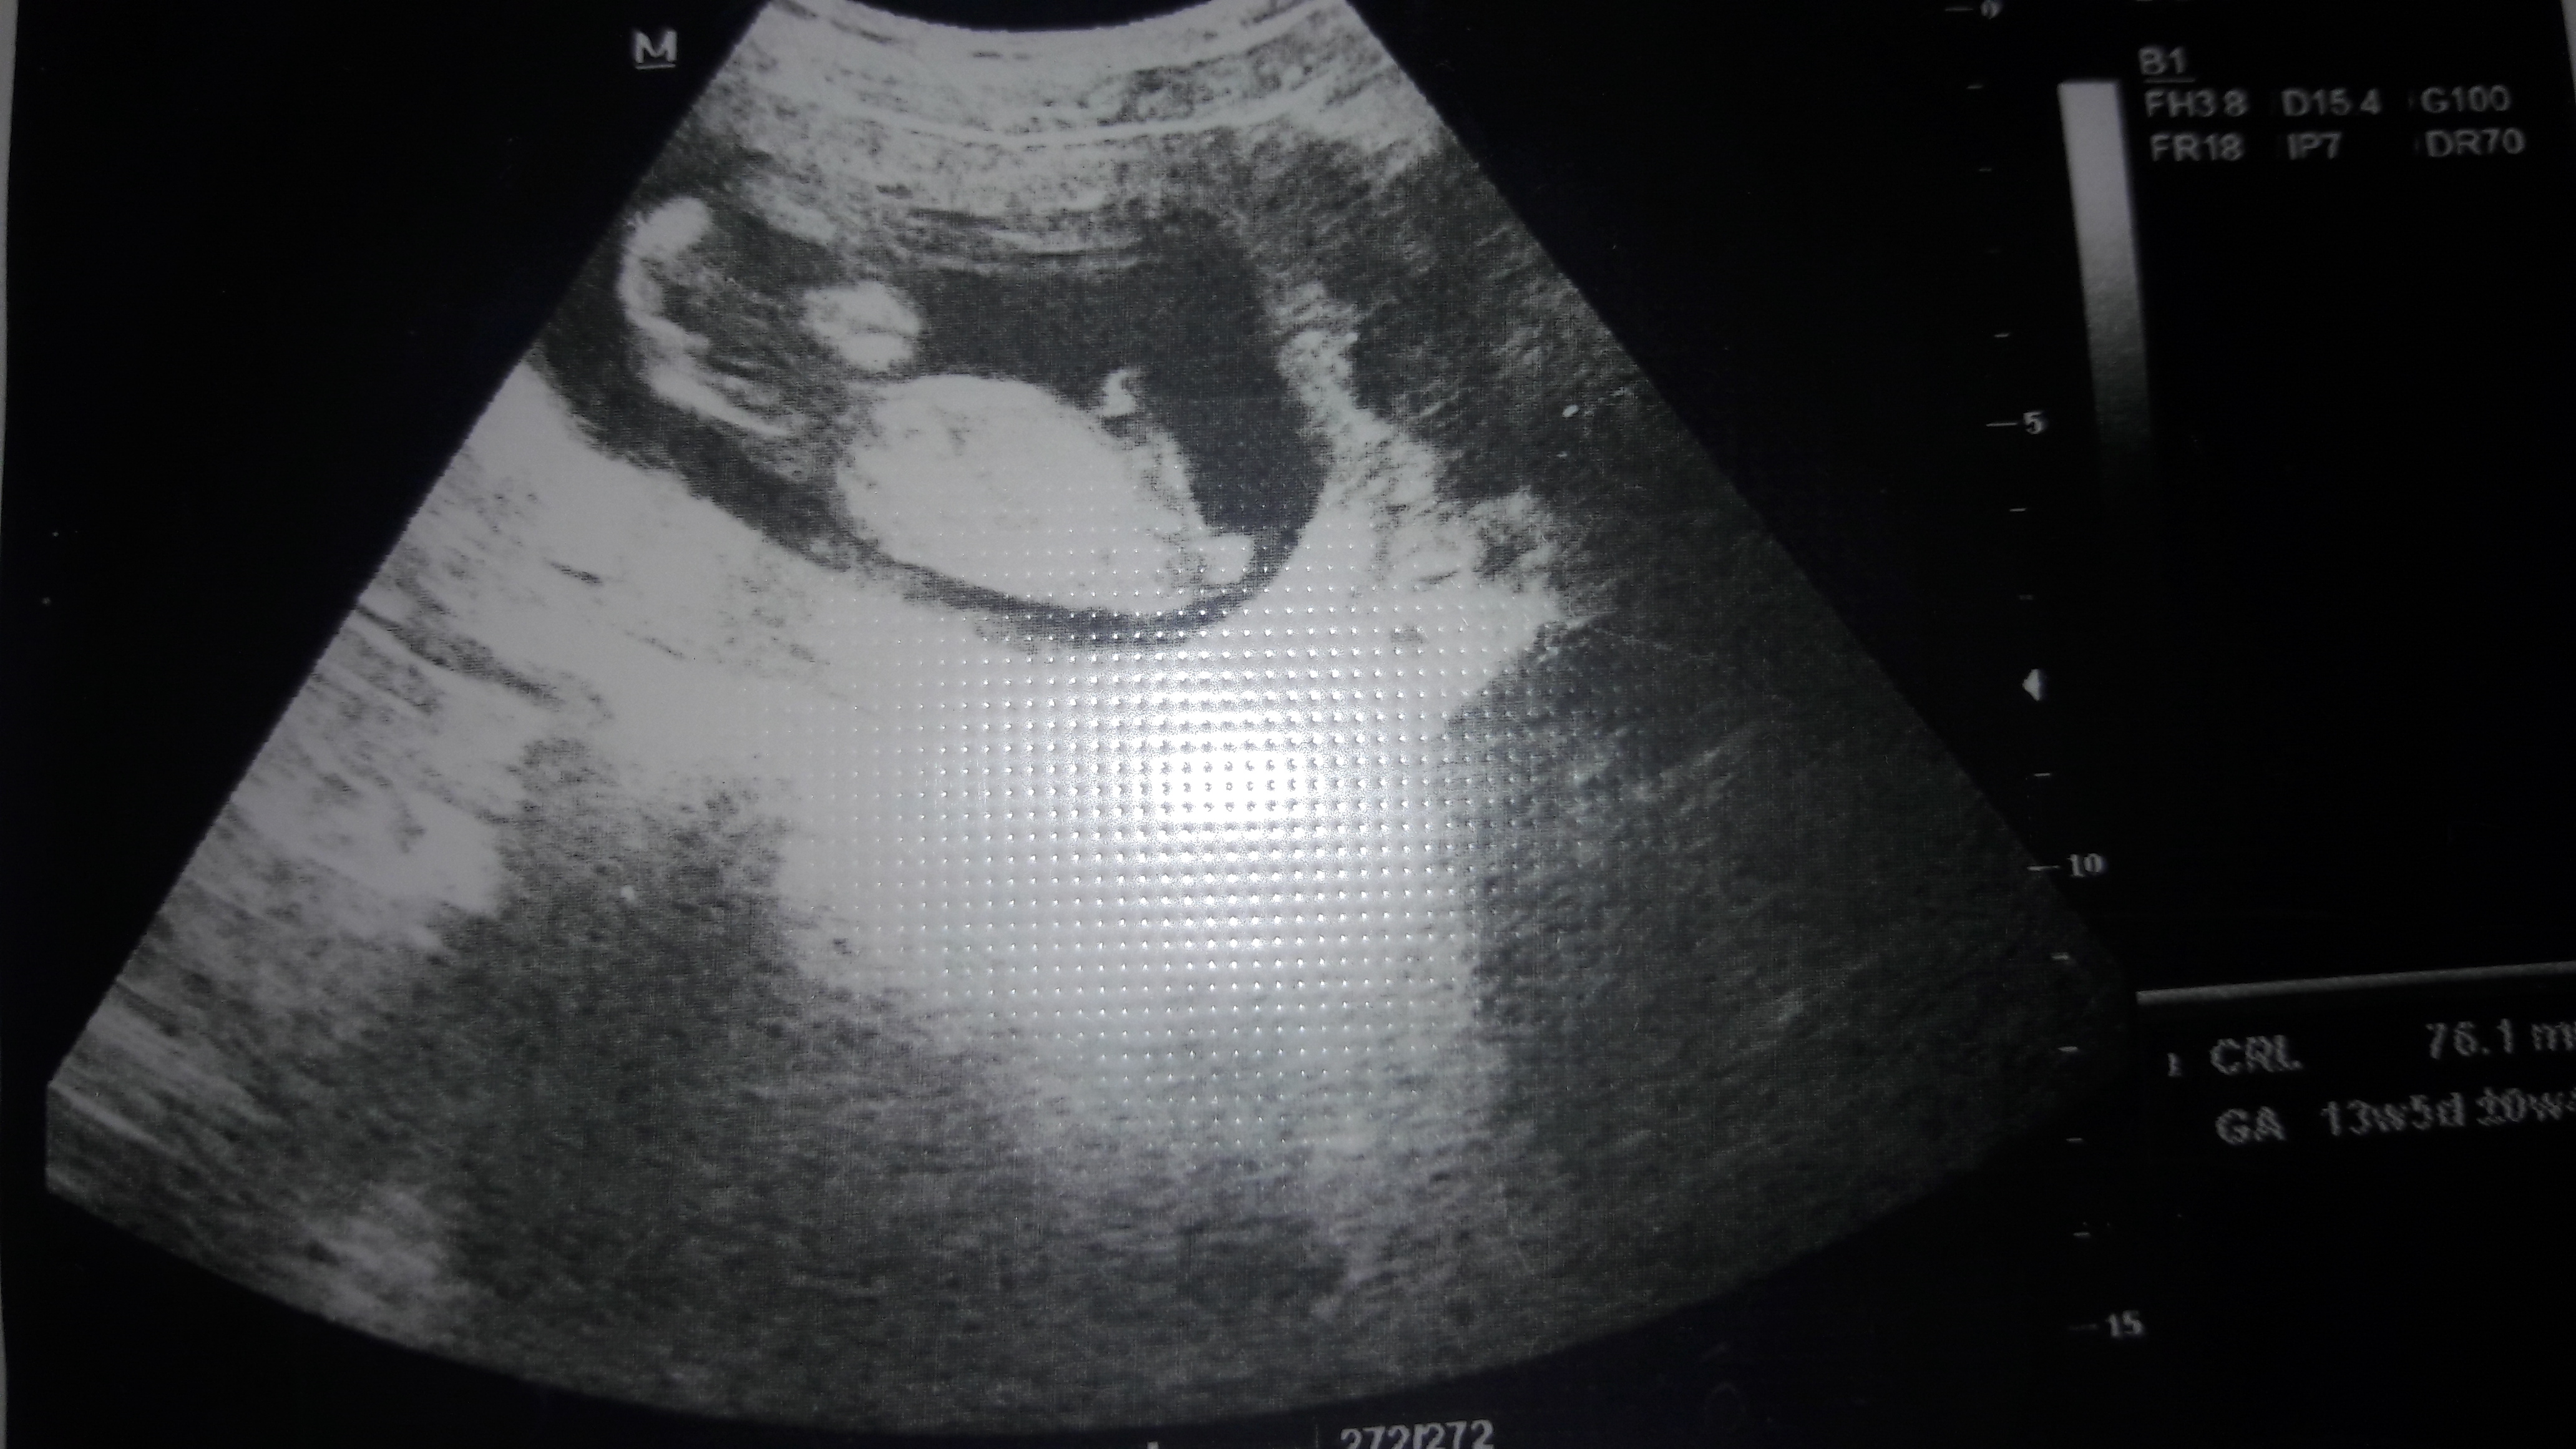

E Eslemimmm Yeni Üye Üye 17 Aralık 2016 #52 Sevimli cadı' Alıntı: Mutlaka yaz bakalım bu nub teorisi ile kaç kişinin bebeğinin cisniyeti tutucak 🙂 Genişletmek için tıkla ... Tamam mutlaka yazacağım arka sayfada 11+2 haftalık resmi de mevcut ona bi arkadaşımız yorum yapmıştı bir de sizden o resime de yorum alabilir miyim

Sevimli cadı' Alıntı: Mutlaka yaz bakalım bu nub teorisi ile kaç kişinin bebeğinin cisniyeti tutucak 🙂 Genişletmek için tıkla ... Tamam mutlaka yazacağım arka sayfada 11+2 haftalık resmi de mevcut ona bi arkadaşımız yorum yapmıştı bir de sizden o resime de yorum alabilir miyim